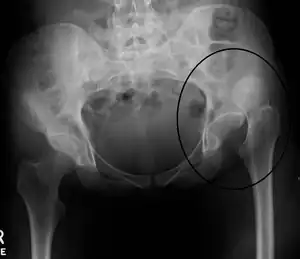

Dislocation of the left hip, secondary to developmental hip dysplasia. Closed arrow marks the acetabulum, open arrow the femoral head.

Hip dysplasia is a condition in which a child is born with a hip problem. Hip dysplasia is when the formation of the hip joint is abnormal. The ball at the top of the thighbone which is known as the femoral head is not stable within the socket (which is also known as the acetabulum).

Hip dysplasia is the preferred term because it provides a more accurate description of the spectrum of abnormalities that affect the immature hip.[20] The term "congenital" dislocation is no longer recommended, except for very rare conditions, in which there is a ("teratologic") fixed dislocation location present at birth.[13]